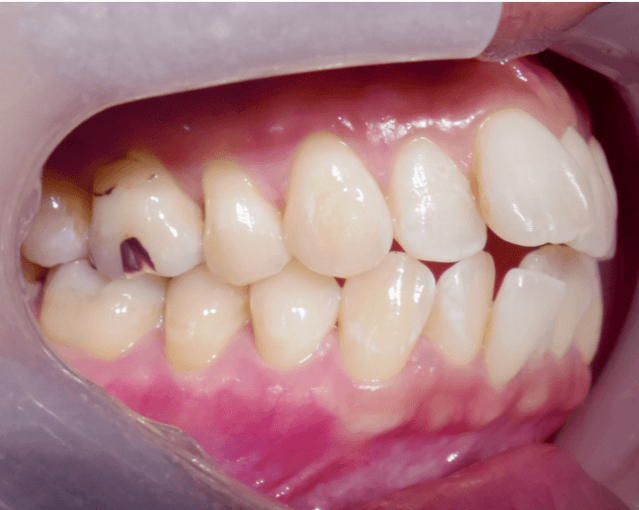

叢生(クロスバイト)

BEFORE

AFTER

担当医コメント

右側の前歯の噛み合わせが逆転している。下顎の正中が右にズレている。下顎の右側前歯を舌側に入れて被蓋を改善し、正中を改善する計画を立てた

治療の概要

年齢/性別

39歳 女性

主訴

前歯の噛み合わせが悪い

リスク

歯肉退縮が起こる可能性がある

費用

82 万円(矯正費用)

+ 22 万円(セラミック費用)

期間

2 2 ヶ月

術前

術中

術後